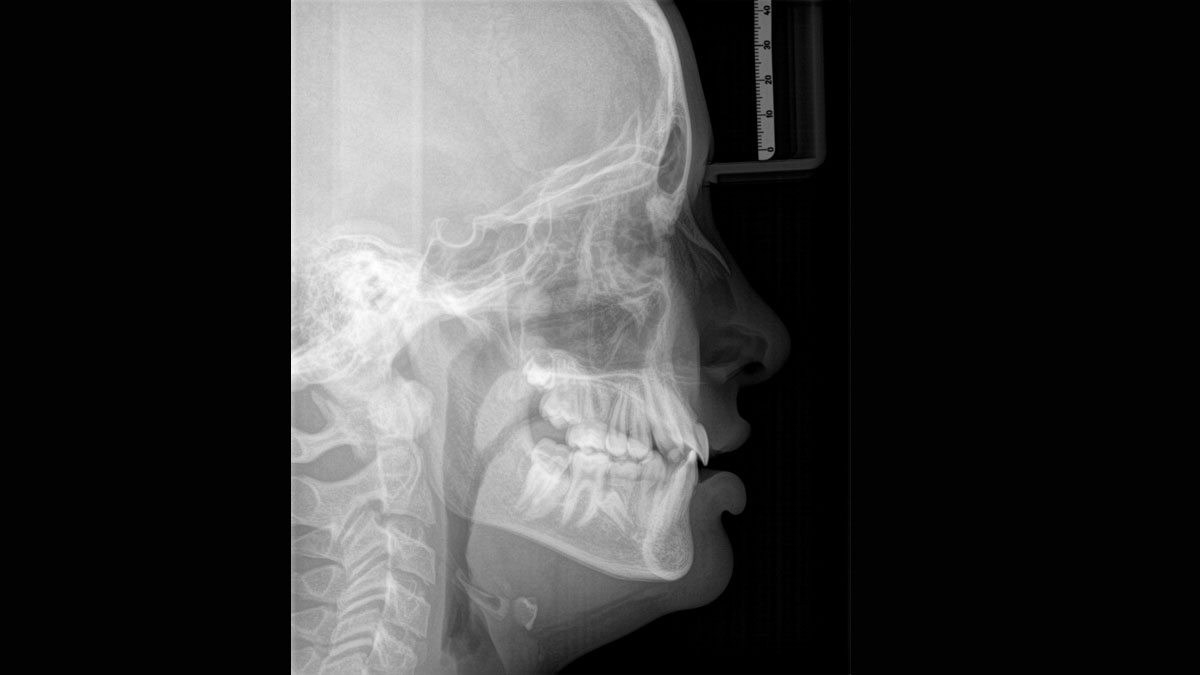

We developed a 10-point concept for easy patient positioning and X-ray imaging. Our concept is primarily about two things: high image quality and comfort for the patient and the assistant. This concept supports and provides the tools needed to ensure high-quality images for treatment analysis and focuses on ergonomics and comfort for the patient and assistant.

The patented bite block technology, for example, automatically establishes the correct inclination of the patient's head, positioning the patient in the occlusal plane, partnering with the 3 point head fixation and firm handles to ensure stable positioning-limiting unnecessary correction scans.